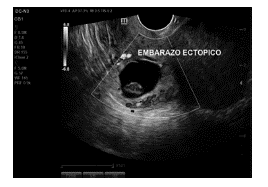

Debido a la localización del saco gestacional y los posibles riesgos secundarios, como son la ruptura uterina, hemorragia severa, la posibilidad de requerir histerectomía secundaria a esta implantación y el riesgo de falla terapéutica con MTX debido a niveles iniciales de BhCG y embriocardia presente, se plantea manejo quirúrgico, sin embargo, con deseo de fertilidad, a pesar de explicar posibles complicaciones, se decide en conjunto intentar manejo farmacológico con MTX, recibiendo una dosis de 80 mg/sm2 el primer y cuarto día. Se realiza seguimiento de la hormona gonadotropina coriónica humana (BhCG), con aumento en los niveles de la hormona, de 37945,60 mUI/ml y en el control eco-gráfico se evidencia persistencia de embriocardia, por lo cual se decide administrar una tercera dosis de MTX. Posterior a esto, se realiza nuevo control ecográfico en el cual se encuentra saco gestacional de 25 mm, localizado en istmo vs. cicatriz uterina previa con presencia de embrión con longitud cráneo caudal de 12.2 mm para un embarazo de 7,3 semanas con actividad cardiaca presente en 139 lpm, sin evidencia de líquido libre (Figuras 2 y 3).